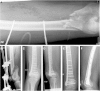

Purpose: Locked plating (LP) of distal femoral fractures has become very popular. Despite technique suggestions from anecdotal and some early reports, knowledge about risk factors for failure, nonunion (NU), and revision is limited. The purpose of this study was to analyze the complications and clinical outcomes of LP treatment for distal femoral fractures.

Materials and methods: From two trauma centers, 243 consecutive surgically treated distal femoral fractures (AO/OTA 33) were retrospectively identified. Of these, 111 fractures in 106 patients (53.8% female) underwent locked plate fixation. They had an average age of 54 years (range 18 to 95 years): 34.2% were obese, 18.9% were smokers, and 18.9% were diabetic. Open fractures were present in 40.5% with 79.5% Gustilo type III. Fixation constructs for plate length, working length, and screw concentration were delineated. Nonunion and/or infection, and implant failure were used as outcome complication variables. Outcome was based on surgical method and addressed according to Pritchett for reduction, range of motion, and pain.

Results: Eighty-three (74.8%) of the fractures healed after the index procedure. Twenty (18.0%) of the patients developed a NU. Four of 20 (20%) resulted in a recalcitrant NU. Length of comminution did not correlate to NU (p = 0.180). Closed injuries had a higher tendency to heal after the index procedure than open injuries (p = 0.057). Closed and minimally open (Gustilo/Anderson types I and II) fractures healed at a significantly higher rate after the index procedure compared to type III open fractures (80.0% versus 61.3%, p = 0.041). Eleven fractures (9.9%) developed hardware failure. Fewer nonunions were found in the submuscular group (10.7%) compared to open reduction (32.0%) (p = 0.023). Fractures above total knee arthroplasties had a significantly greater rate of failed hardware (p = 0.040) and worse clinical outcome according to Pritchett (p = 0.040). Loss of fixation was related to pain (F = 3.19, p = 0.046) and a tendency to worse outcome (F = 2.43, p = 0.071). No relationship was found between nonunion and working length.

Conclusion: Despite modern fixation techniques, distal femoral fractures often result in persistent disability and worse clinical outcomes. Soft tissue management seems to be important. Submuscular plate insertion reduced the nonunion rate. Preexisting total knee arthroplasty increased the risk of hardware failure. Further studies determining factors that improve outcome are warranted.